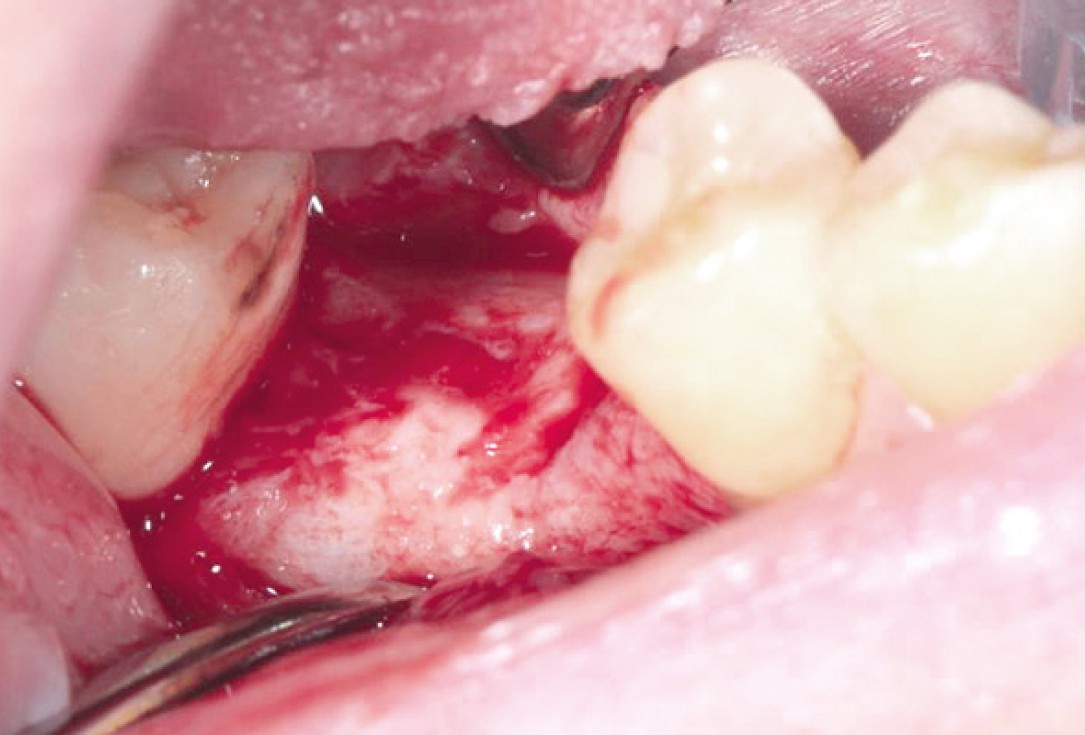

Situation after tooth extraction.